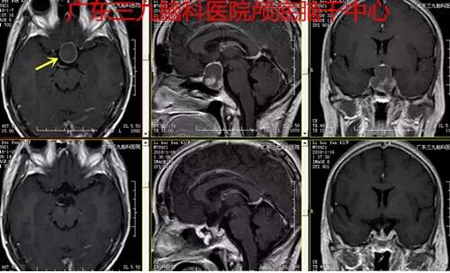

▲图4:术前术后磁共振对比肿瘤切除